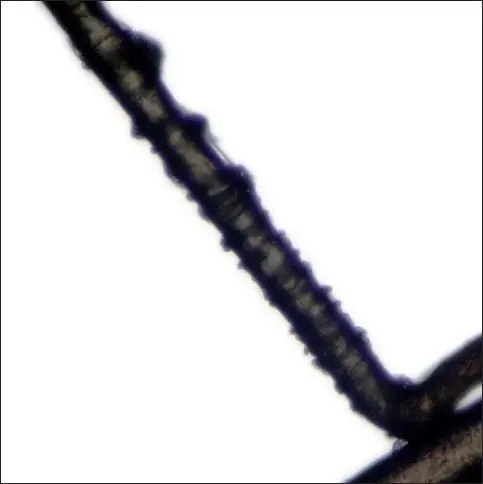

Additionally, closer examination of such hairs can reveal certain peculiarities. For instance, the bulbs of such hair are misshapen. Moreover, the cuticle of the hair looks ruffled.

Dhurat RP, Deshpande DJ. Loose anagen hair syndrome. Int J Trichology. 2010 Jul;2(2):96-100. doi: 10.4103/0974-7753.77513. PMID: 21712911; PMCID: PMC3107966/Creative Commons License